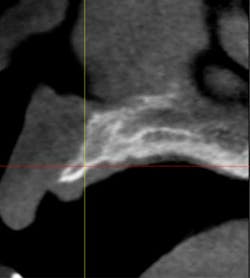

Fig. 7